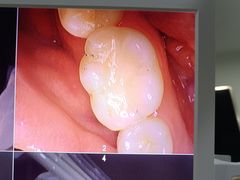

• 土豆口腔(凤凰北总店)

• -土豆口腔(凤凰北总店)

金文博_5274 | 24-11-01